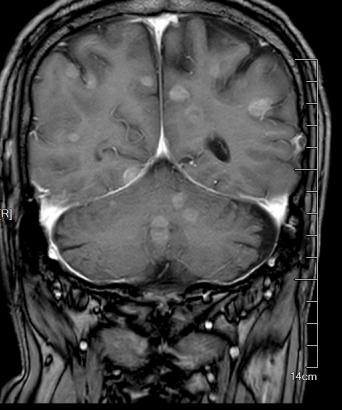

△颅内密密麻麻分布着转移灶,最大的有核桃大

为进一步排查其他部位转移,庄主任随即安排了头颅MRI检查,患者颅内密密麻麻分布着十余处转移灶,最大的直径达3cm,最小的仅5mm,如同隐藏在脑部的定时炸弹。

“患者ECOG评分(体力状态评分)为2分,进食日渐困难,情况非常不乐观。”庄兴俊主任介绍,就像打仗一样,肺部主战场已经失守,肿瘤弥漫性转移,大脑里密密麻麻布满转移灶,最大的有核桃大小。肺癌引发的全身性危机,尤其是脑转移引发颅内高压,直接威胁生命中枢,必须立刻处理。